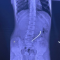

Ребенок поступил в клинику с «острым животом». Инородные тела повредили желудочно-кишечный тракт. Несколько магнитов соединились между собой в различных сегментах внутренних органов.

— Очень редкое сочетание: одни магниты находились в желудке, другие — в начальном отделе тонкой кишки. Это привело к образованию фистулы — сообщению между желудком и кишкой, — написал Юрий Козлов.